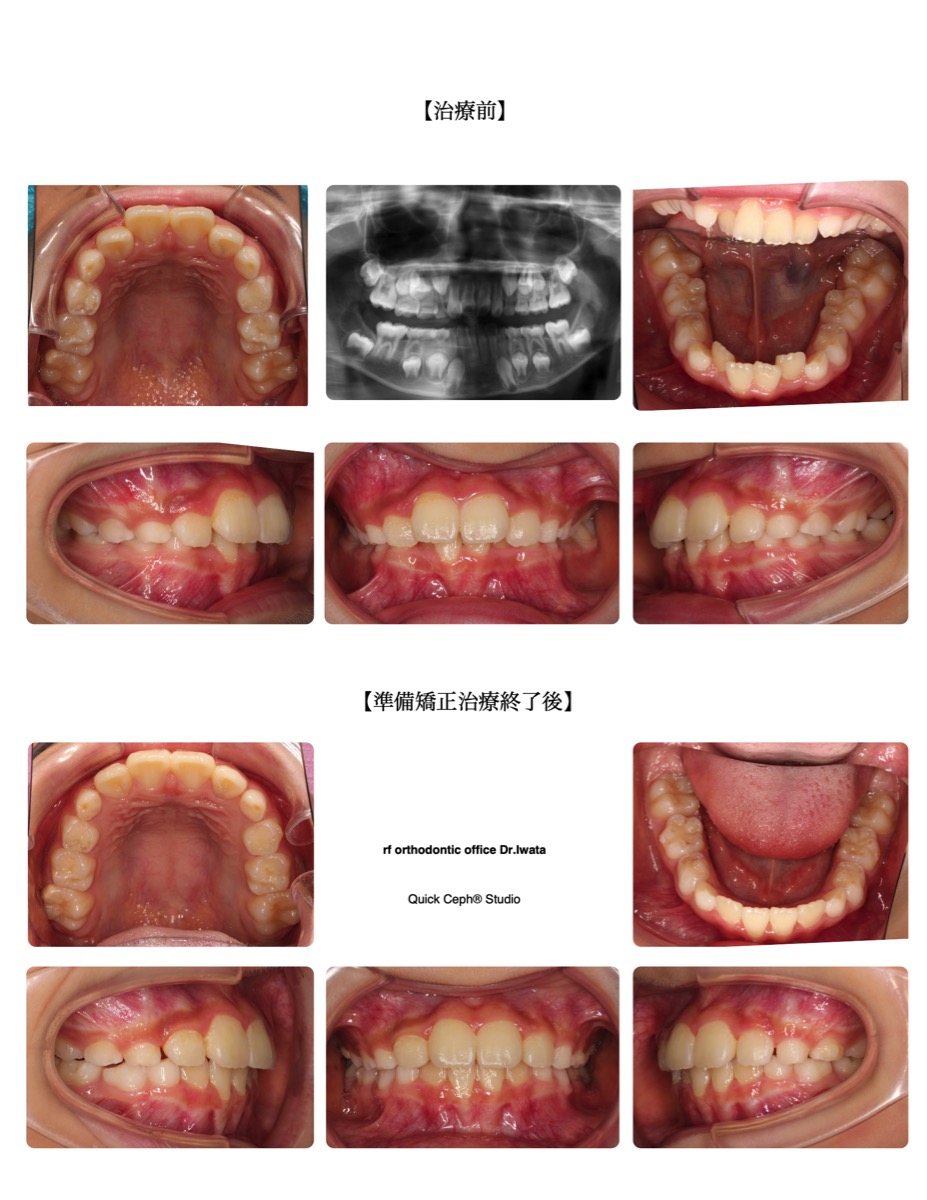

case3

受け口

下の前歯が上の前歯より前に出ている噛み合わせ。